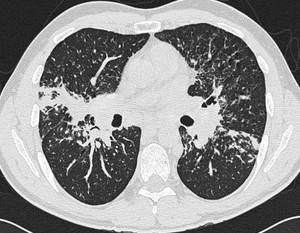

Визуализация и диагностика неинвазивного аспергиллеза с помощью КТ

Раздел: Необычные решения